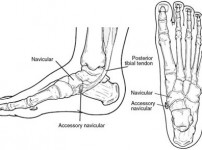

부주상골증후군

운동할 때 복숭아뼈 통증? 미사 정형외과에서 말하는 부주상골증후군 자가진단법

1. 복숭아뼈 안쪽이 유독 튀어나오고 아프다면?새해를 맞아 운동을 시작했는데 갑자기 발 안쪽, 특히 복숭아뼈 아래쪽이 붓고 아픈 경험이 있으신가요? 단순히 새 신발 때문이거나 근육…

5시간 전